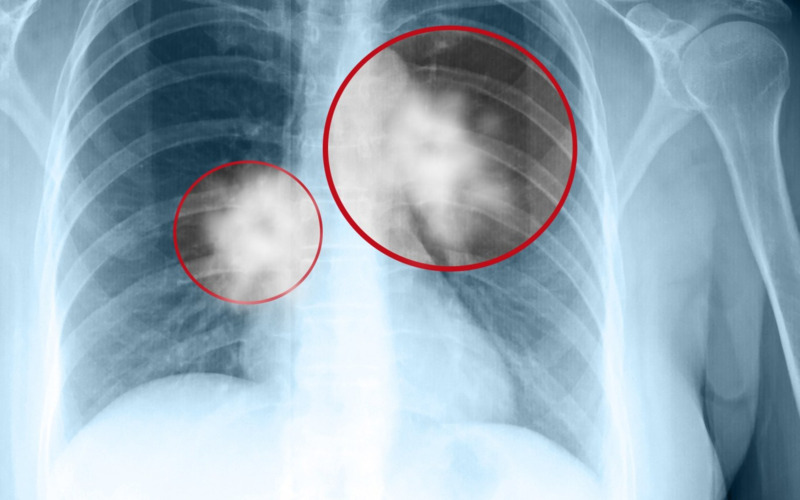

Anh Wang nhìn vào những nốt kính mờ trên phim chụp mà lòng như lửa đốt. Anh không giữ được bình tĩnh, suýt chút nữa thì làm loạn cả bệnh viện đòi phẫu thuật cho con. Đến khi được bác sĩ từ tốn giải thích kỹ, anh mới vỡ lẽ. Vừa ôm con trai khóc trong vui mừng, vừa rối rít xin lỗi đội ngũ y bác sĩ.

Sự mâu thuẫn này thực chất dựa trên những chỉ số y khoa rất cụ thể. Khối u của bé Xiao Chen chỉ rộng 8 milimét, là dạng kính mờ thuần túy, không có hàm lượng chất rắn.

Bác sĩ giải thích rằng, Tổ chức Y tế Thế giới đã loại loại tổn thương này khỏi danh sách u ác tính xâm lấn và coi đây chỉ là tổn thương tiền ung thư hoặc lành tính dựa trên loại nốt. Ngay cả trong số các nốt ác tính, hầu hết là ung thư phổi "lành tính" hoặc giai đoạn rất sớm với tiên lượng tốt. Chúng có tốc độ phát triển cực chậm, có khi mất hàng chục năm vẫn đứng yên, hầu như không đe dọa đến tính mạng.

- Kích thước nốt mờ tăng nhanh vượt mức 1cm.

- Nốt mờ xuất hiện phần đặc bên trong (chuyển sang dạng hỗn hợp).

- Bờ nốt mờ không còn mịn mà có hình răng cưa hoặc tua gai.

Nếu không có các dấu hiệu này, gia đình chỉ cần theo dõi định kỳ.

Không phải nốt kính mờ nào ở phổi cũng là dấu hiệu của khối u ác tính (Ảnh minh họa)